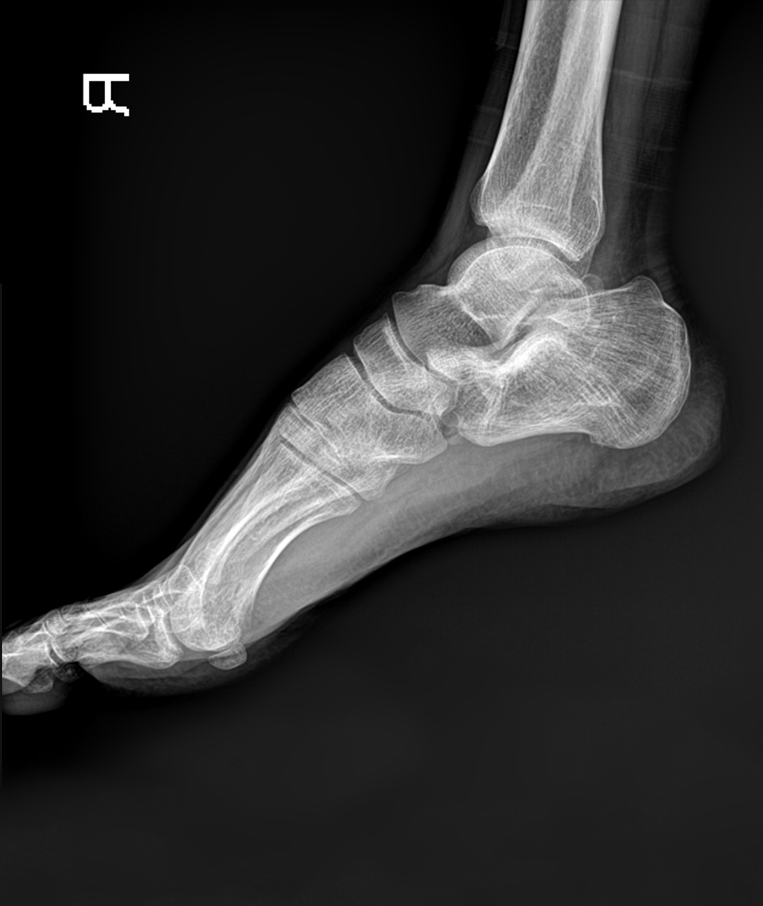

Clinical picture

临床图片